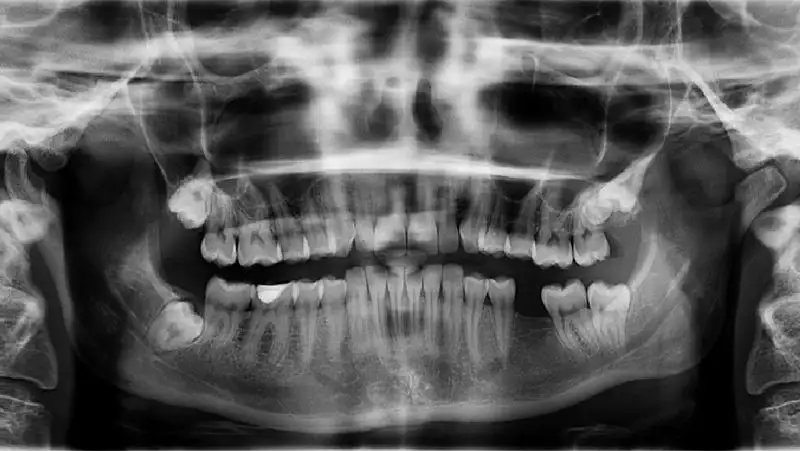

Правильный прикус, фото - Новости Zakon.kz от 11.09.2022 14:03 Фото: pixabay

Привычка спать на животе или на боку с открытым ртом приводит к постоянному давлению на одну сторону лица, сообщает Zakon.kz.

Частый сон на боку или на животе может привести к изменению положения зубов и формы лица. Об этом сообщил стоматолог Николай Ожерельев, сообщает URA.RU.

Со временем такое давление может вызвать изменение положения зубов и, как следствие, формы лица. Также не стоит подкладывать под лицо руку. Так как это приводит к неравномерной нагрузке на зубы и деформации прикуса.Николай Ожерельев

Прикус нарушится и в случае, если вы спите без подушки. Правильная подушка должна обеспечивать поддержку так, чтобы шея была расположена параллельно матрасу.